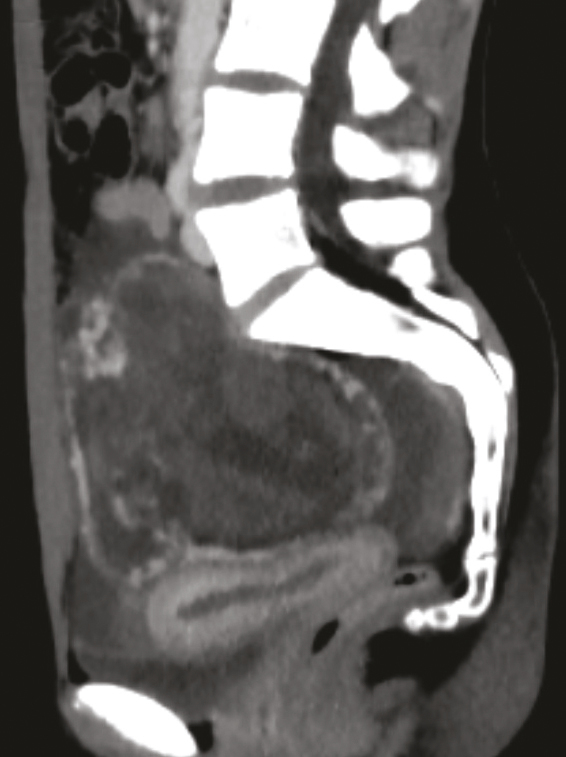

Cette jeune fille de 16 ans était admise aux urgences pour une hémorragie interne, en état de choc. Elle avait reçu un coup de sabot de cheval dans le bas ventre. La tomodensitométrie abdomino-pelvienne montrait un épanchement intra-abdominal abondant et une masse hétérogène au niveau du pelvis avec une extravasation de produit de contraste en faveur d’un saignement actif et évoquant une contusion mésentérico-intestinale (fig. 1 ). L’état hémodynamique de la patiente s’étant déstabilisé, une laparotomie était décidée ; l’application de deux pinces de Bengoléa sur les vaisseaux rompus (fig. 2 et 3 ) permettait de contrôler l’hémorragie. Devant une modification architecturale manifeste de l’ovaire, une annexectomie non conservatrice était réalisée. Les suites opératoires étaient normales. L’anatomopathologie était en faveur d’une tumeur stromale bénigne. Une déclaration systématique dans le réseau national des tumeurs rares de l’ovaire de l’Institut national du cancer était faite.